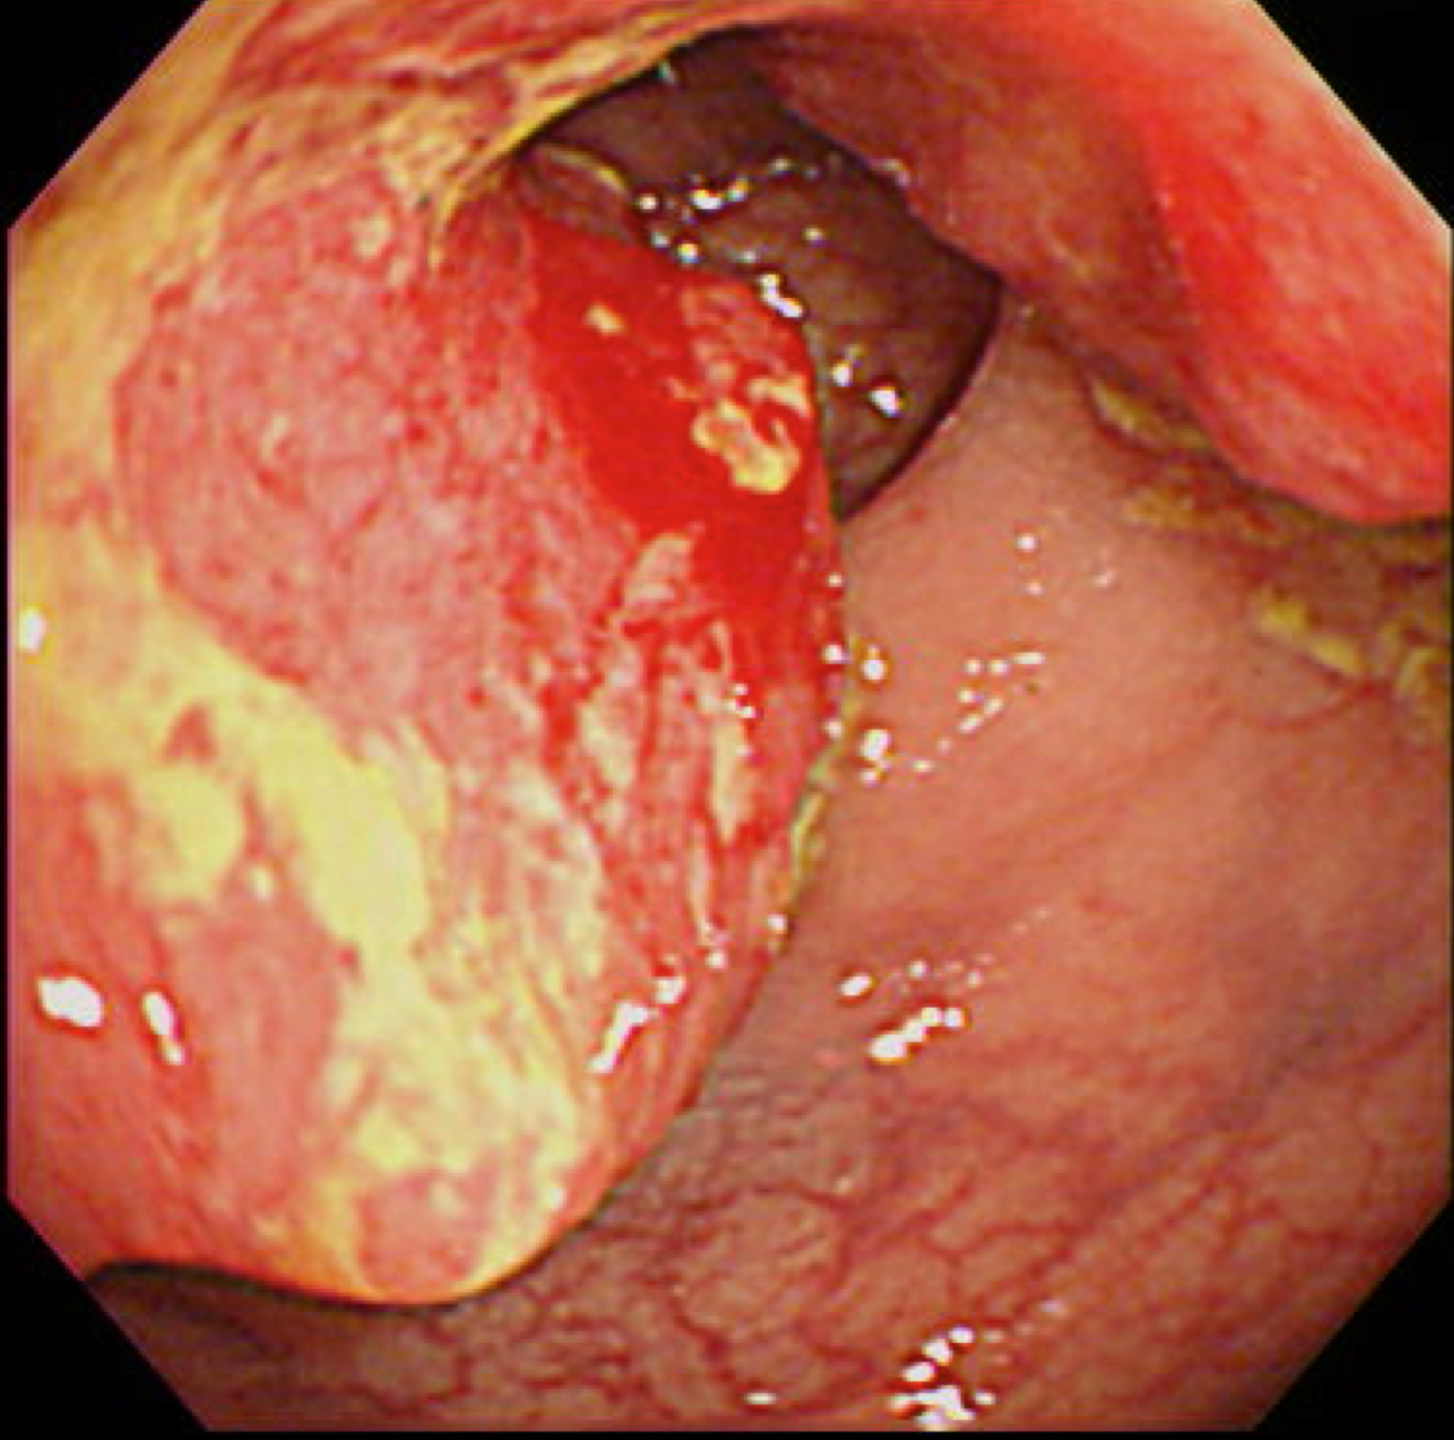

大腸がん(S状結腸癌)

大腸がん検診

大腸がん検診は検便(便中ヒトヘモグロビン検査2日法)でおこないます。

検便を2日間連続で採取し、その中のヒトヘモグロビン濃度を測定します。大腸がんも日本人に増えているがんです。

もし陽性であれば、何らかの病気がある可能性があると判断されますので、大腸の検査をおこなうことになります。

写真は過去に当院でおこなった大腸内視鏡で発見された癌ですが、現在は当院では大腸内視鏡をおこなっておりません。そのため検査をおこなう医療機関へ紹介させていただきます。